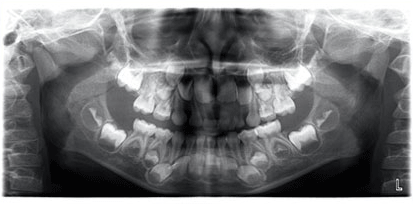

Digital x-rays are one of the most wonderful advances in dental technology! We are super excited about our new Planmecca digital panorex unit. It has the most advanced technology to date.

We have digital intra-oral sensors for regular x-rays and now we can take digital panorex x-rays of the whole jaw, for the orthodontist, to check growth and development, evaluate wisdom molars. And best yet, for kids with a sensitive gag reflex

we can now take bitewing x-rays from outside the mouth with NO sensors necessary in the mouth.